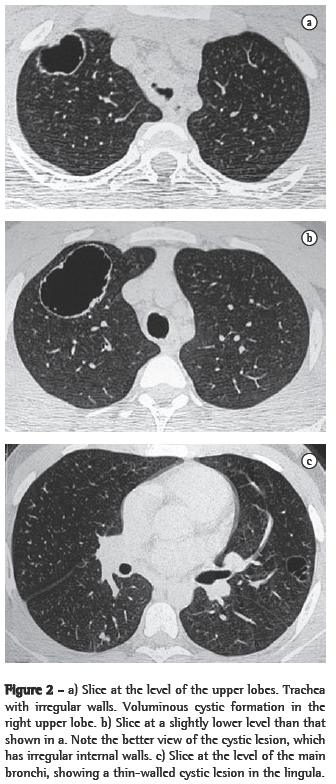

In all eight cases, the CT scans revealed polypoid formations in the trachea. In one case, injury to one of the main bronchi was identified. Seven patients presented involvement of the pulmonary parenchyma. In all eight cases, there were cavitated polypoid lesions, with irregular internal borders and walls of various thicknesses, multilobulated in six cases and presenting confluence of the lesions in five (Figures 1 through 5). Solid nodules were seen in six patients. An air-fluid level was observed in only one patient. The lesions were predominantly in the lung bases in three patients and in the middle thirds in two, whereas they were evenly distributed in two. In one patient, the lesions were accompanied by a mass, and, in another patient, they were accompanied by consolidation. In the latter case (Figure 5), there was malignant degeneration in multiple lesions. Signs of air trapping were also observed in one case. There were no identified instances of lymph node enlargement or pleural effusion.

Chest X-rays are inferior to CT scans of the chest, especially those performed using spiral CT (volumetric acquisition), in the initial phases of pulmonary dissemination, due to the fact that CT better characterizes and allows better visualization of nodular tracheobronchial vegetation, Tomographic findings include focal or diffuse airway narrowing caused by the nodules. The nodules form on the mucosal surface, and their invasion into the lumen is best evaluated using CT.(3) These alterations are easily correlated with the disease when there is a clinical history of papillomatosis.(4) Other findings related to airway obstruction and accompanying infections are atelectasis, consolidations, air trapping and bronchiectasis.(2-4) In our sample, polypoid formations in the trachea were observed on all of the CT scans Seven patients presented involvement of the pulmonary parenchyma, characterized by cavitated polypoid lesions with irregular internal borders and walls of various thicknesses, with a multilobulated aspect and a tendency toward confluence. Solid nodules were seen in six patients. None of the patients presented lymph node enlargement or pleural effusion.